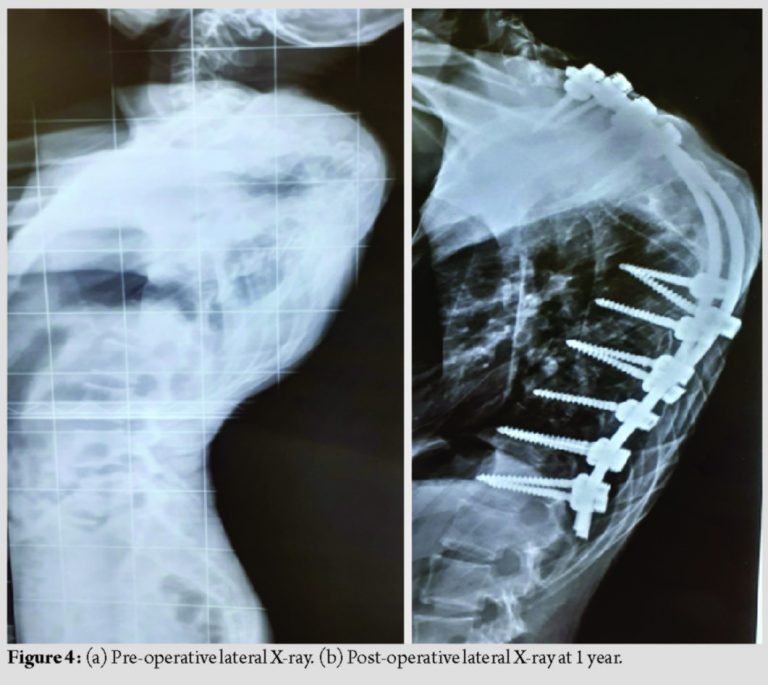

Copious amounts of morselized autologous bone graft were placed posteriorly to promote posterior bony fusion. Time for surgery was 4.5 h. Blood loss was 800 ml. There were no intraoperative adverse events. The post-operative period was uneventful. Kyphosis was corrected from 100° to 65° and scoliosis (Coronal Cobbs angle) was corrected from 100° to 60°. The patient was back to full functional status. At 1-year follow-up, good fusion was achieved, as seen on the X-ray (Fig. 3a and b and 4a and b).

There was no coronal or sagittal imbalance at end of 1 year and upper back hump was cosmetically better compared to pre-operative (Fig. 5a and b) (Fig. 6a and b).

NF-1 is an autosomal dominant disorder. Scoliosis is seen in about 10–64% of NF-1 [1,3]. The prevalence of NF-1 is 1:3000 [8,9]. Curves are dystrophic or non-dystrophic type. Non-dystrophic curves usually present like idiopathic scoliosis [10]. Tsirikos et al. [11] reported that dystrophic curves <20° should be closely observed and a sudden progression in the curve should be considered for surgery. Dystrophic curves more than 20° generally require surgery. The approach for surgery in such patients remains unresolved. The choice is between a combined anterior plus posterior fusion and an all posterior fusion. Kim and Weinstein [12] believed that dystrophic scoliotic curves of 20–40° and kyphosis <50° can be managed with posterior spinal instrumented fusion only. To obtain better correction and avoid pseudoarthrosis, anteroposterior fusion was recommended when dystrophic scoliosis was greater than 40° and/or kyphosis was greater than 50°. The efficacy of anterior surgery is often compromised due to hyperkyphosis and vertebral rotation according to some authors [3,13]. The presence of tumor or excessive plexiform venous channels around the vertebral bodies sometimes makes it impossible to approach the apex of the curve anteriorly. Due to dystrophy, apical vertebrae can be significantly subluxated and malaligned from rest of the spine. Such malalignment does not allow anterior strut grafts to be placed in the concavity of the kyphosis, and hence, they are mechanically ineffective in preventing its progression [14]. Some authors have described the use of pre-operative halo gravity traction, especially in rotatory subluxation of vertebrae in NF-1 dystrophic curve to minimize risk of correction surgery, improve flexibility of the curve and pre-operative pulmonary function [6,7]. We concluded that pre-operative traction in such a patient may not be as effective in distracting the apex of the deformity as there was partial fusion observed at the apex of the deformity, especially the D5-D6 vertebra. In our opinion, the purpose of surgery in these cases is to stabilize the vertebral column and halt further progression of deformity rather than aiming for full correction of the curve. We believe that kyphosis correction through the anterior approach would have been difficult, in such a lesion in the upper thoracic spine due to the deep, high apex, and crowding of the vital structures around this region. We also observed in the radiological investigations that the dysplastic vertebra of D5 was posteriorly sequestered with the vertebra of D4 and D6 partially covering it anteriorly. In our opinion, the access to the D5 vertebra in such a situation would have been less than adequate anteriorly, leading to the possibility of incomplete excision of the D5 vertebra and the posterior bony knuckle caused by it. According to the recently published guidelines of management of kyphosis by Rajasekaran et al., this patient was considered to be a Type III B type of kyphosis [15]. The authors recommended doing a posterior vertebrectomy and posterior fixation with or without a pre-operative halo gravity traction. Keeping in mind the aim of our surgery to stabilize the kyphosis and prevent further progression of the deformity, along with removing the offending bony knuckle of the D5 vertebra causing the pressure on the cord, we chose to do a three column osteotomy at the apex D5 level and posterior fixation from C7 to T2 and T8-L1 fixation along with titanium rods. We did not excise the whole of the D5 body, but left behind the endplates of the D5 body, on which the osteotomy was closed. This we chose to do keeping in mind the higher rates of pseudoarthrosis in NF-1. We tried to eliminate the need of a metallic mesh cage with autologous bone graft and instead chose to keep the native bone to bone contact and augmented the posterior fusion bed with the remaining autologous bone. We managed to achieve an acceptable kyphosis correction from 100° to 65° and scoliosis correction from 100° to 60°. These measurements remained same at the end of 1 year follow-up with a good fusion status, as seen on the X-ray. There was excellent cosmetic improvement of the upper back deformity and no further progression of the myelopathy in the patient. The limitations of this report are the short period of post-operative follow-up and lack of documentation of the fusion status by a CT scan. We usually avoid doing regular CT scans on our patients when we observe on the X-ray that there is no implant loosening, loss of correction, or progression of the deformity.